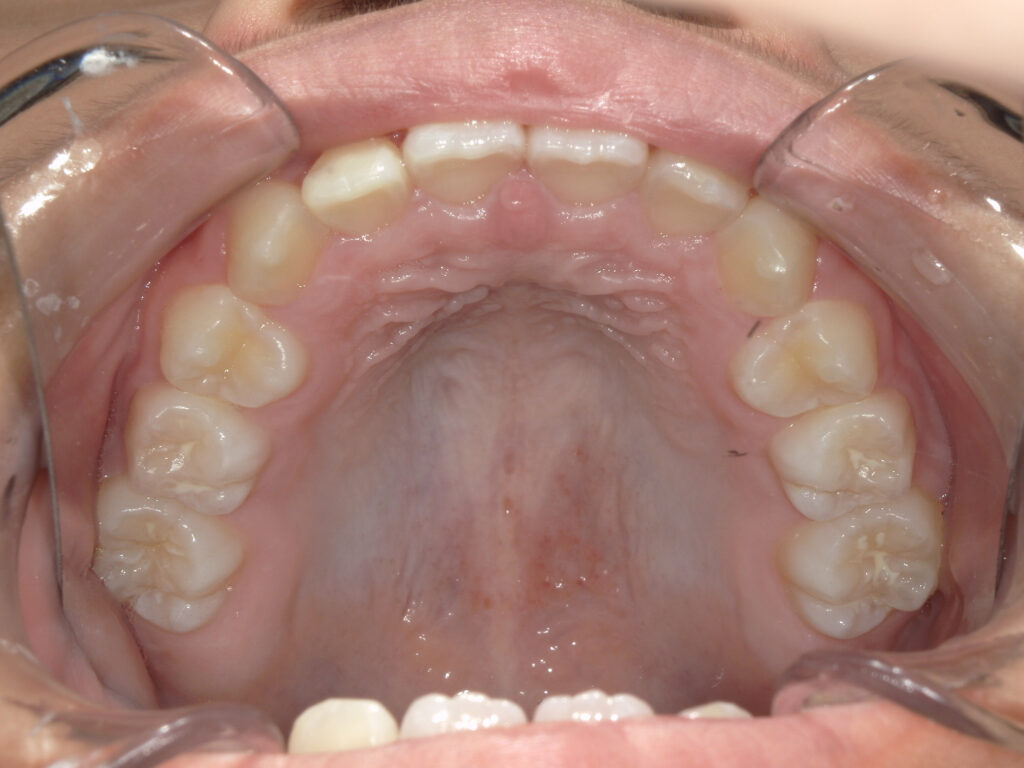

上顎

治療後